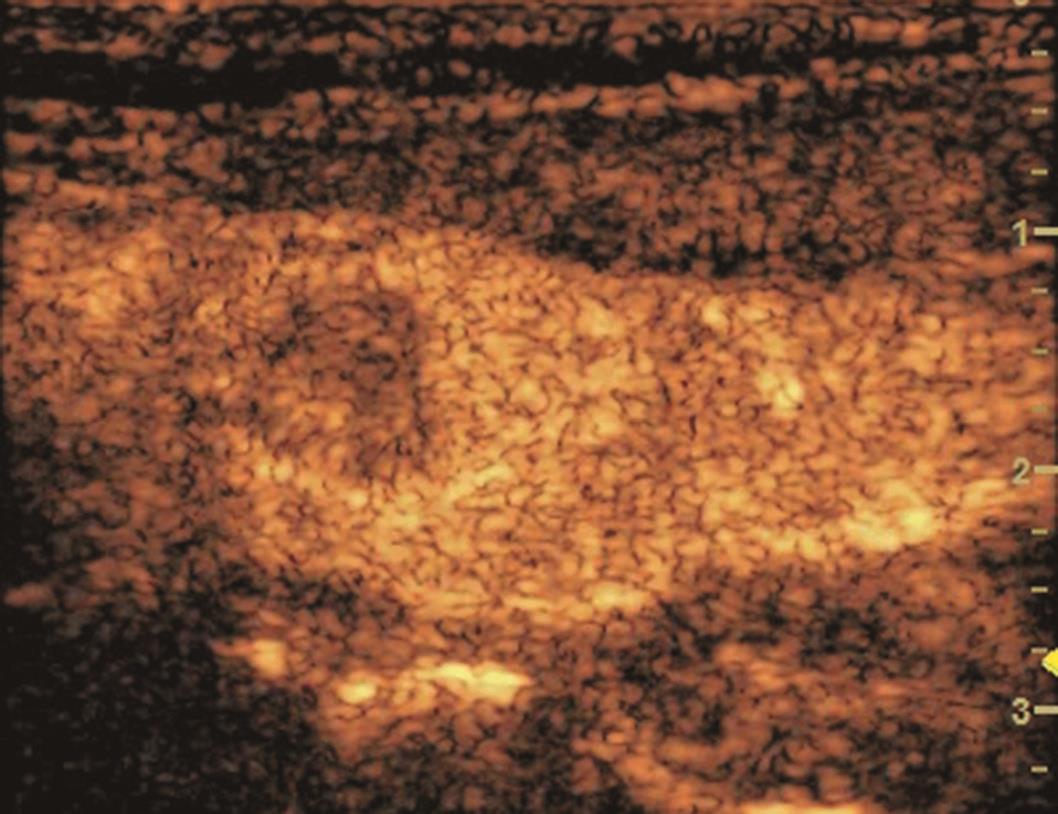

甲状腺左叶中下部见一混合回声结节,边界清,形态规则,中心部可见斑状强回声,CDFI显示周边可见环状血流信号,其内可见丰富血流信号,见图1-3-18。

该结节早于周围腺体组织增强,结节内部呈高增强表现,可见部分无增强区;结节晚于周围腺体组织消退,仍呈高增强表现;结节周边可见均匀高增强环,甲状腺被膜未见明显中断,见图1-3-19、ER1-3-9。

(1)结节增强早期早于腺体增强或与腺体同步增强,增强晚期晚于腺体消退或与腺体同步消退。

(2)结节内部呈均匀或不均匀弥漫性等增强或高增强,增强水平通常高于周围腺体。

(3)结节与周围腺体分界清晰,形态较规则。

(4)部分结节周边可见均匀高增强环。

(5)结节周边被膜连续完整。

甲状腺滤泡性腺瘤通常为富血供病灶,其增强水平等于或高于周围腺体,并呈现“早增强,晚消退”的特点,重点需要与滤泡性腺癌鉴别,腺瘤多边界清晰、形态较规则,造影时结节周围的高增强环厚薄一致、较为均匀,结节周边被膜连续完整、无浸润表现,颈部淋巴结无异常肿大等。而滤泡性腺癌边界不清、呈浸润性生长表现,周边高增强环消失或厚薄不均,如发现颈部异常肿大淋巴结及被膜连续性中断等,需要高度警惕甲状腺恶性肿瘤。